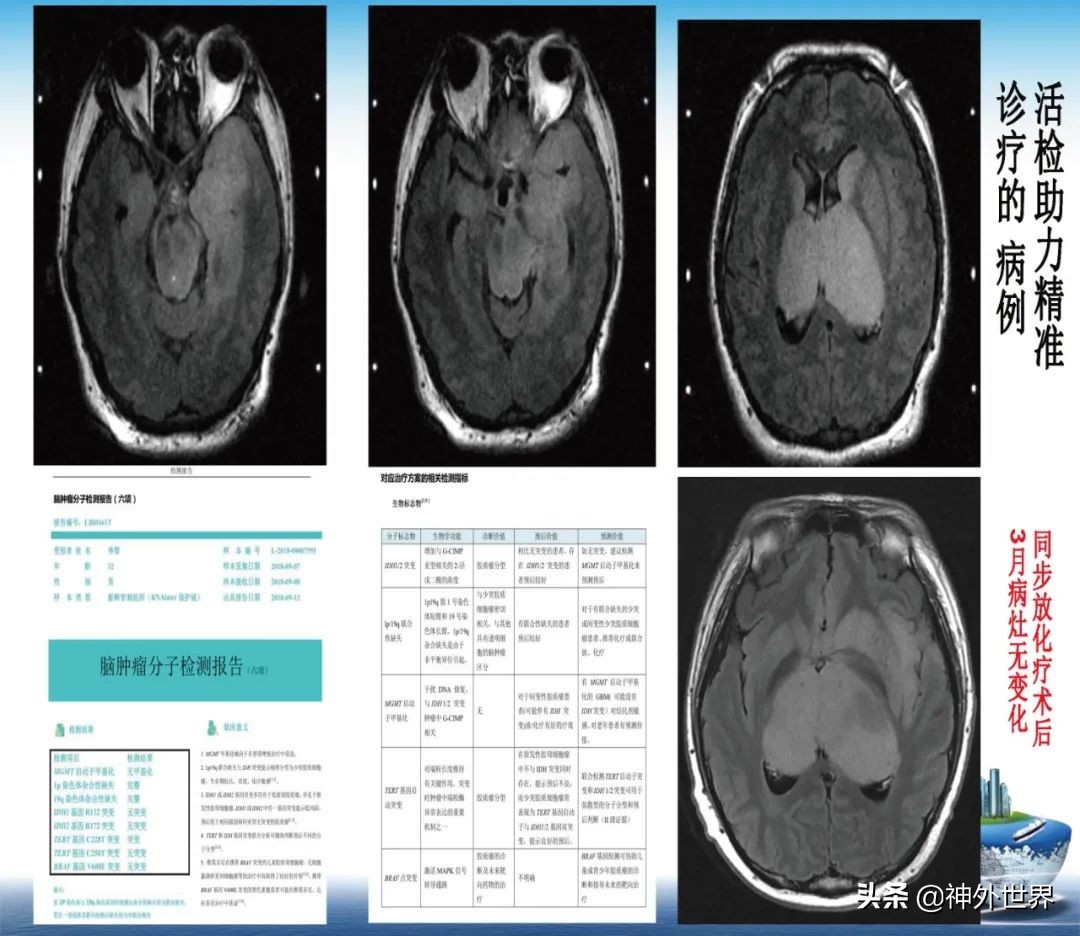

专业方向:颅内肿瘤的显微外科手术切除,颅咽管瘤综合治疗具有特色;在立体定向脑内病灶活检、立体定向清除脑干血肿、立体定向间质内放疗、机器人辅助神经外科手术方面具有专长。